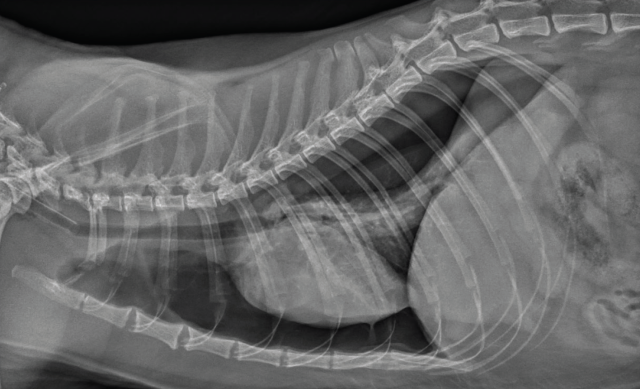

Many causes of dyspnoea are possible, and localisation is key in determining the required intervention. Thoracic trauma is common in these patients, even when there are no other visible injuries. Respiratory rate alone should not be used to exclude significant thoracic trauma and ideally survey radiographs should be performed in all patients (Figures 1 and 2) (Sigrist 2004). Table 1 gives some possible physical examination abnormalities with differentials and suggestions for diagnostics.